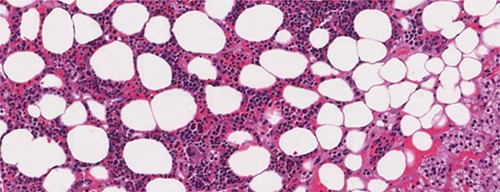

A 26-year-old female patient, presented with right flank pain evolving for 4 months. The clinical examination showed a morbid obesity with a body mass index of 42.8, a pulse at 85 bpm and normal blood pressure of 125/85 mmHg. CT showed a right retroperitoneal mass measuring 11 × 7 cm on the axial plane with a large axis of 9 cm. The mass appeared largely fatty with areas of higher attenuation inside. Density on CT varied between −90 Hounsfield units (HU) peripherally and −30 HU in the center (Fig. 1). Laboratory investigations were normal. A screening hormone test related to the adrenal gland revealed normal plasma catecholamine levels; epinephrine, 0.07 ng/ml (N: 0.00–0.10); norepinephrine, 0.28 ng/ml (N: 0.10–0.50). Furthermore, detailed 24-h urinalyses during hospitalization showed normal urinary catecholamine levels. The rest of the endocrine exploration was normal. The patient was taken up for exploratory laparotomy. Intraoperatively, a giant solid mass was found arising from the right adrenal gland and was adherent the upper pole of the kidney, duodenum and liver. The patient underwent excision of this adrenal mass. Macroscopically, the mass measured 12 × 8 × 10 cm and was round, well circumscribed and encapsulated. Histologically, the tumor was confirmed as a myelolipoma, and no malignant foci were detected (Fig. 2). The patient had an uneventful recovery and was discharged on the fifth post-operative day. Six months following the surgery the patient had no significant complaints and reported that her right flank pain had since subsided.

Microscopic appearance of adrenal myelolipoma; typical histological features of a myelolipoma comprising adipose tissue mixed with areas of hematopoietic tissue.